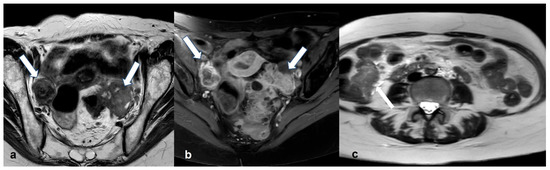

2.1.4. Endometrioid Carcinoma and Clear Cell Carcinoma

2.5.2. Decidualized Endometrioma